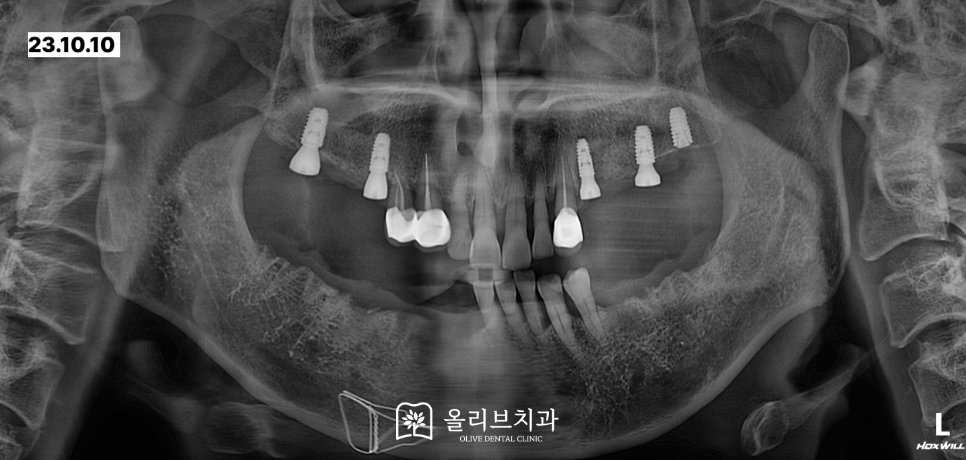

전체적인 상태를 체크하기 위해서 촬영한 파노라마 x-ray입니다. 위쪽의 큰 어금니들은 내원하셨을 때 이미 상실된 상태였습니다.

상악 우측 작은어금니는 뿌리만 남아있으며 상악 좌측 작은 어금니에는 뿌리 끝 염증이 발생해 있었습니다.

x-ray상에서 보면 하악의 치아가 위치한 치주부분들이 좋지 않아 잇몸뼈가 많이 내려간 상태여서 치아가 전반적으로 흔들리는 상황이었습니다.